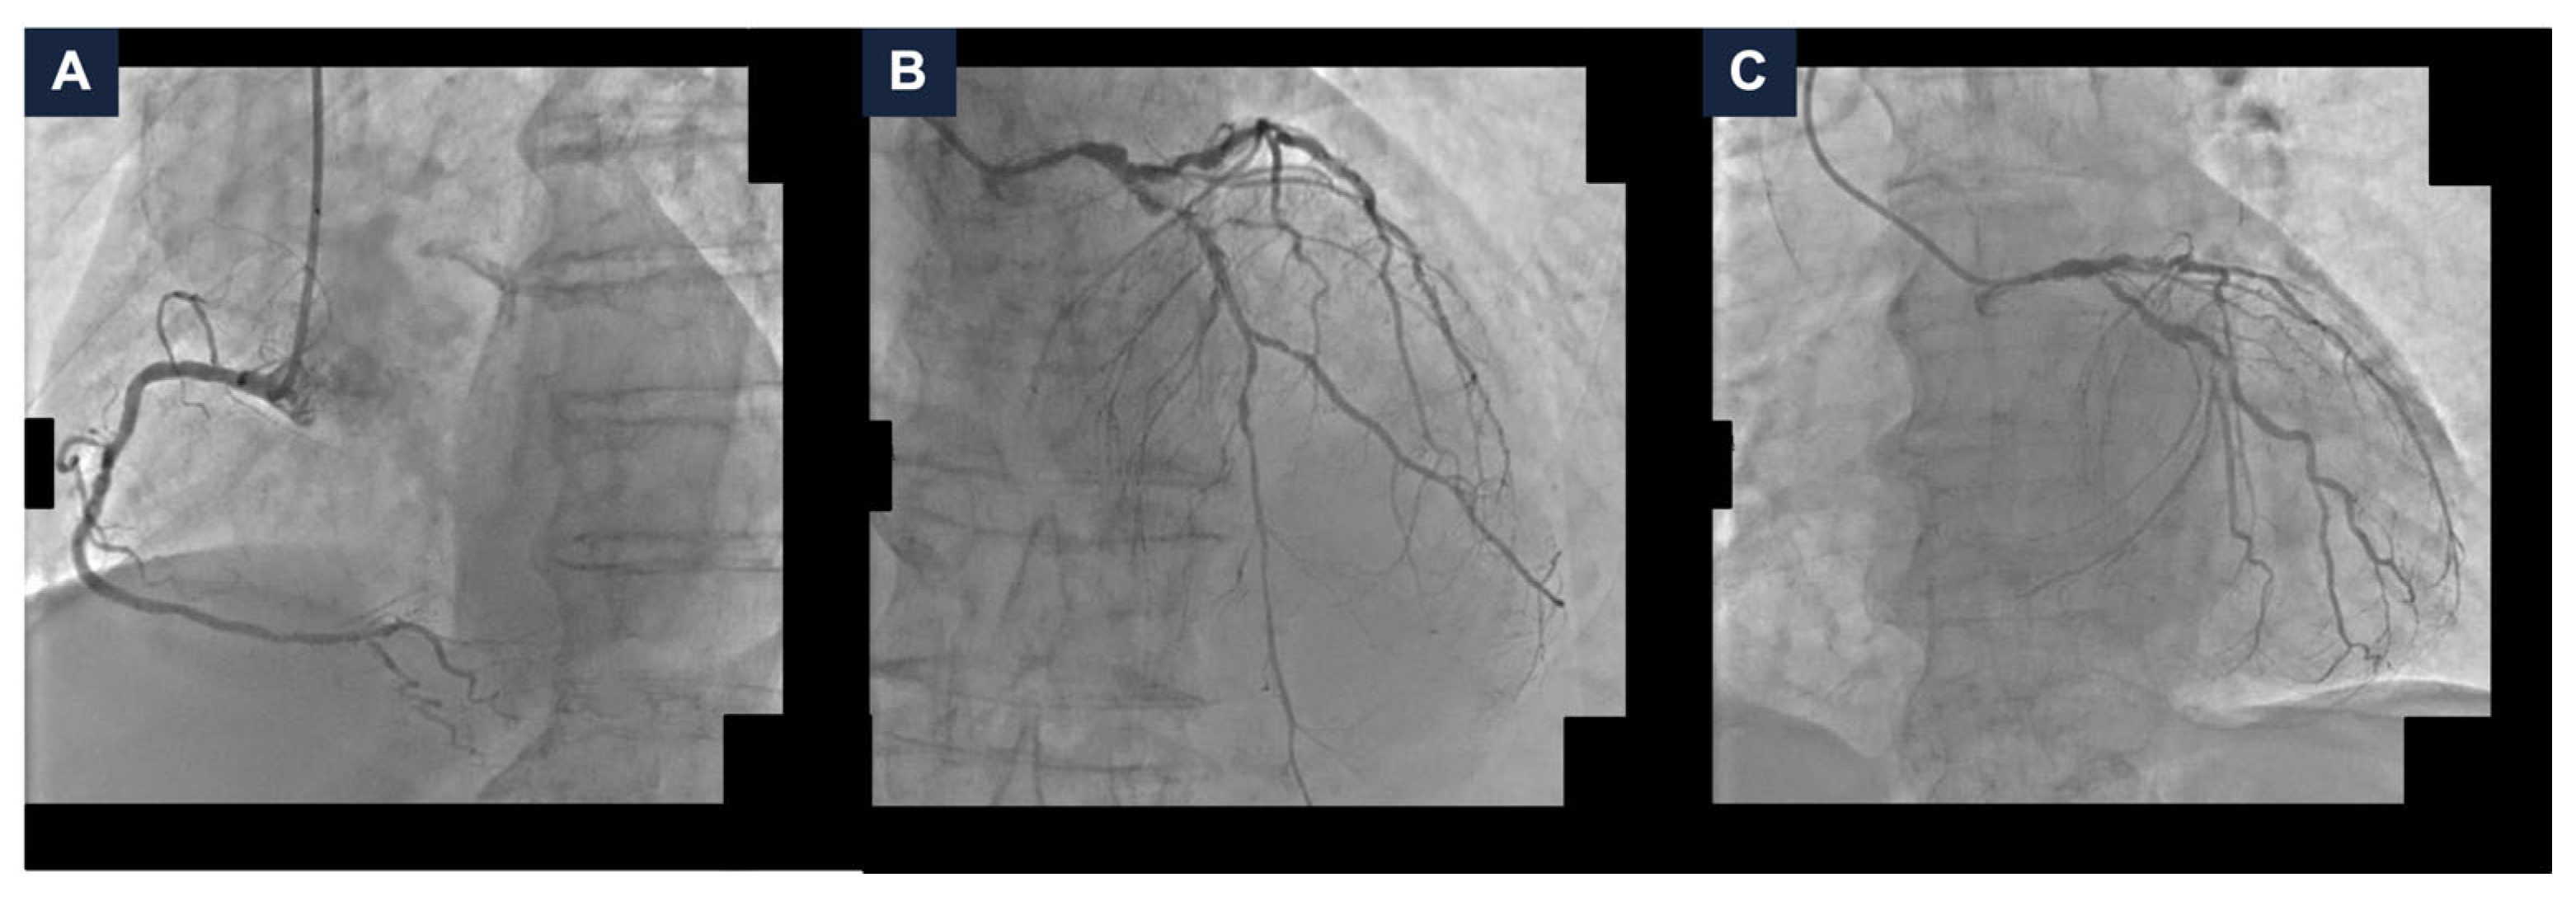

A 95-year-old man with hypertension and hyperlipidemia was admitted to our hospital with Non-ST-segment elevation myocardial infarction (NSTEMI). His medical history was positive for chronic obstructive pulmonary disease and stage IV chronic kidney disease (the estimated glomerular filtration rate (eGFR) at hospitalization was 28 mL/min/1.73 m2). No other relevant comorbidities were reported, and he had very good cognitive and geriatric conditions. Transthoracic echocardiography was performed and revealed a moderately hypertrophic left ventricle, akinesis of the apex and anterior interventricular septum, hypokinesis of the anterior and anterolateral walls, and a left ventricular ejection fraction (LVEF) of 33%; the right ventricle had normal dimensions with a tricuspid annular plane systolic excursion of 19 mm; the mitral and tricuspid valves had moderate regurgitation, and the estimated systolic pulmonary artery pressure was 40 mmHg. Coronary angiography was scheduled. It showed a dominant right coronary artery, with a good development and caliber, and no critical stenoses. The left coronary artery had a good caliber and development, too. It presented a heavily calcified, critical stenosis of the ostial left main coronary artery (LMCA), along with multiple, severely calcified, sub-occlusive stenoses of the ostial left circumflex artery (LCx) and the proximal left anterior descending artery (LAD), and several, highly calcified, critical stenoses of the mid LAD and proximal LCx (Figure 1, panel A–C and Video S1). After the coronary angiography, a comprehensive clinical and technical evaluation of the patient’s conditions was performed, in order to determine the best therapeutic and prognostic strategy. The most relevant clinical and technical elements were as follows: the patient’s very active lifestyle, with no relevant clinical comorbidities that could have given him an unfavorable prognosis; the multiple, heavily calcified, sub-occlusive and critical stenoses of the LMCA-LAD-LCx bifurcation, that had a strong prognostic impact; and the severely depressed systolic function of the left ventricle, which conferred to the revascularization an even higher risk. MCS-assisted PCI of the LMCA-LAD-LCx bifurcation was proposed, in order to offer a prognostic benefit. The patient initially refused. Therefore, the hospitalization was extended in order to optimize the medical therapy. Antihypertensive agents (Amlodipine, Bisoprolol, and Doxazosin) and diuretics (Furosemide and Canrenone) were titrated while renal function and serum potassium levels were monitored to ensure safety and efficacy. Thus, the patient was discharged on a dual antiplatelet therapy with Ticagrelor 180 mg/day and Acetylsalicylic Acid 100 mg/day, Amlodipine 10 mg/day, Bisoprolol 5 mg/day, Furosemide 50 mg/day, Canrenone 50 mg/day, Doxazosin 8 mg/day, and a dual hypolipidemic therapy with Atorvastatin 20 mg/day and Ezetimibe 10 mg/day (at hospital discharge, the eGFR was 25 mL/min/1.73 m2). Two weeks later, due to persistent refractory angina at rest, the patient agreed to proceed with the scheduled intervention and was readmitted. At the time of the second hospitalization, the eGFR was 16 mL/min/1.73 m2; consequently, Canrenone was suspended.

Figure 1.

Baseline coronary angiography. (A) Right coronary artery angiography demonstrating no critical stenoses. (B,C) Left coronary artery angiography in cranial (panel B) and caudal (panel C) views showing severe, heavily calcified, sub-occlusive and critical stenoses of the left main coronary artery, proximal and mid left anterior descending artery, and ostial and proximal left circumflex artery.